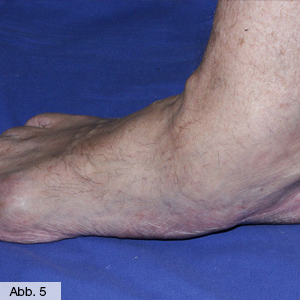

Knick-Senkfuß

Dies ist eine typische Deformität des Rückfußes (Abb. 5). Im Allgemeinen verursacht er keine Beschwerden oder es kann durch Einlagen zumindest eine Verschlimmerung verhindert werden. In schweren Fällen kommt es zu Belastungsschmerzen oder zum Hervortreten eines Knochens (Kahnbein) an der Innenseite des Fußes.

Bei Kindern ist eine operative Therapie dann recht einfach: durch eine so genannte Arthorise (Calcaneus-Stop-Schraube, Abb. 6) kann ein weiteres Absinken des Fußgewölbes gestoppt werden und das Gewölbe normalisiert sich bis zur Aufrichtung. Dieser einfache Eingriff kann an beiden Füßen gleichzeitig durchgeführt werden und erfordert einen nur ein- bis zweitägigen stationären Aufenthalt.

Bei Erwachsenen ist die Korrektur aufwendiger: je nach Ausprägung der Deformität, Alter des Patienten und Situation des unteren Sprunggelenks können wir einen Knickfuß des Erwachsenen durch Sehnenverlagerung und Versetzung des Fersenfortsatzes oder durch eine korrigierende Versteifung des unteren Sprunggelenks behandeln.